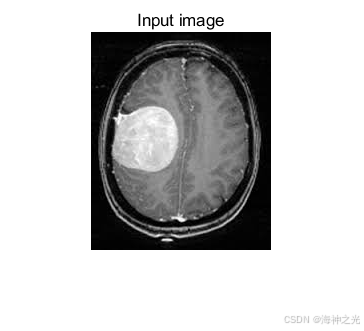

⛄一、各向异性扩散滤波器大脑MRI图像肿瘤识别

2 MRI肿瘤识别流程

1. 预处理阶段

各向异性扩散用于去噪,抑制MRI中的Rician噪声。通过多次迭代调整扩散系数,在均匀区域平滑噪声,在肿瘤边缘(高梯度区域)停止扩散。